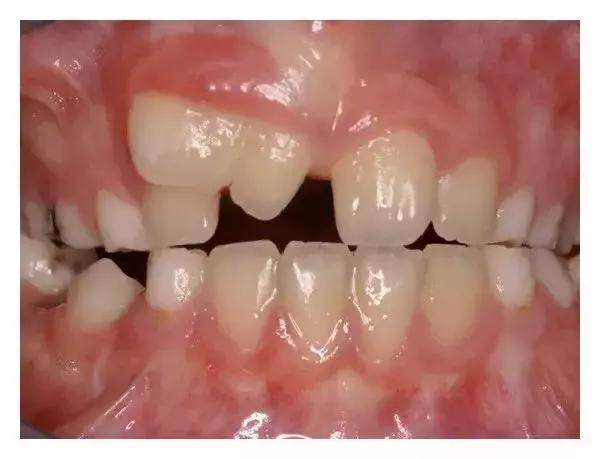

如果孩子长了一些看上去不太正常的牙齿,父母更是万分担心。比如,像这个孩子:

孩子刚长出两颗上门牙的时候,家长发现他的左边牙齿(图中右侧)是正常的,但右边的牙齿看着就像两颗牙齿连在了一起。

家长感到困惑了:这是什么?到底是一颗牙齿还是两颗牙齿呢?其实,真的不好判断。我们需要等到孩子旁边的乳牙也长出来了,才好“下定论”。

一年以后,孩子的其他上前牙也相继地萌出。看图数数,如果把孩子连着一起的牙齿当作是一颗牙的话,孩子正好有4颗上前牙,数目上符合牙齿生长规律。这类型的双牙畸形属于双生牙。